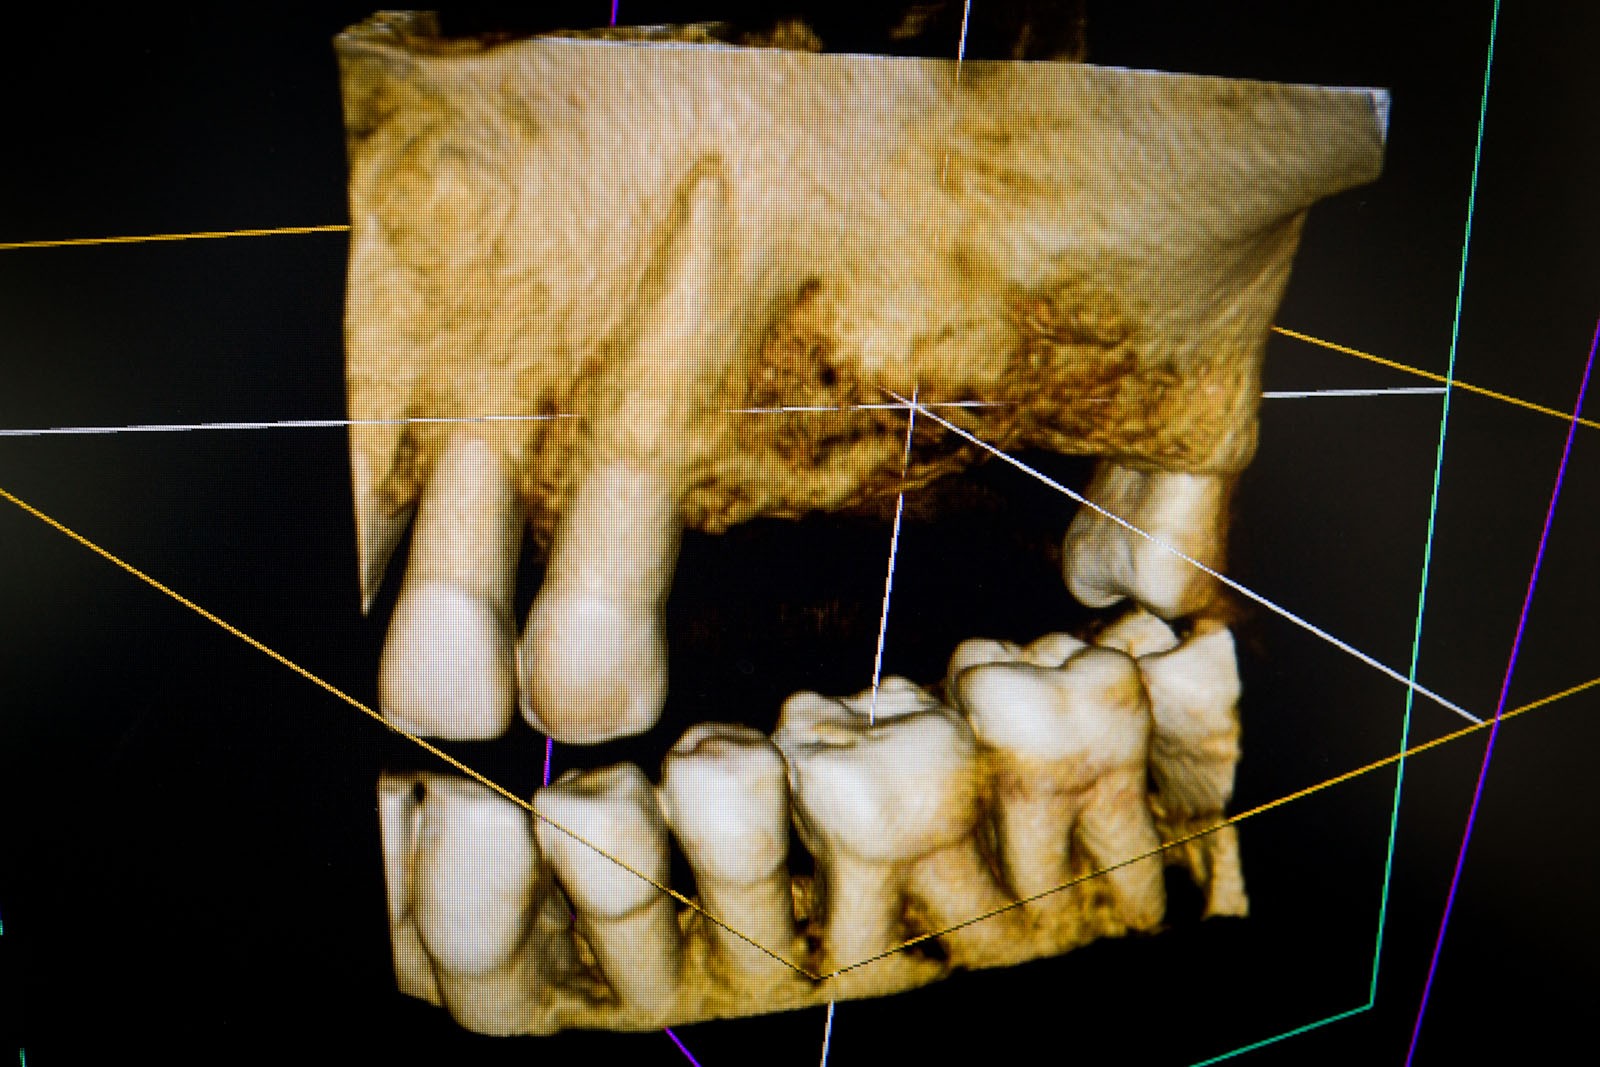

Przed podjęciem leczenia należy określić stopień zaniku kości szczęk oraz żuchwy. W tym celu przeprowadza się badanie kliniczne oraz odpowiednią diagnostykę obrazową pacjenta. Uwzględnia ona zdjęcie panoramiczne OPG jako podstawę dwuwymiarowego obrazowania podłoża kostnego oraz możliwe jest badanie tomograficzne CT lub bardziej precyzyjna tomografia stożkowa CBCT. Opcjonalnie wykorzystywana diagnostycznie tomografia pozwala na bardziej wnikliwą ocenę stopnia zaniku kości w trójwymiarowym, przestrzennym obrazie.

Precyzja projektu druku siatki bazuje na dokładności odwzorowania kształtu kości w stożkowej tomografii komputerowej CBCT, co zapewnia ich dobre przyleganie do podłoża kostnego oraz ogranicza powstawanie powikłań w postaci obnażania się siatek.